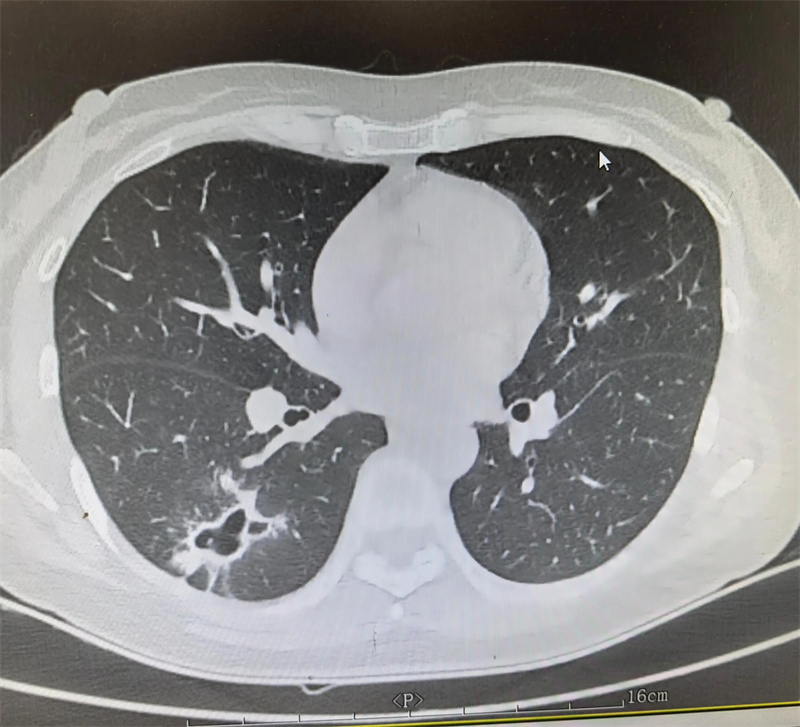

胸外科(二疗区)主任田子刚受邀参与,结合艾利影像学检查、肺功能评估及全身基础状况,与孙集思主任团队反复研讨手术指征、手术方式及围手术期风险防控要点。经过充分论证,最终确定实施“右肺下叶切除手术”。

△图片非案例所提及